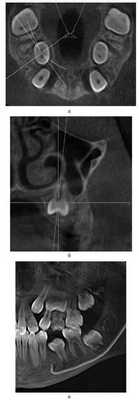

Кроме компактного размещения зачатков зубов или их корней в альвеолярном отростке, при уменьшенном размере челюстей изменения касаются и самого альвеолярного отростка; он тоже более компактно располагается в области зачатков или корней зубов. Если зачаток зуба находится глубоко в альвеолярном отростке, форма последнего на КТ в поперечном срезе может напоминать трапецию, у которой меньшая из сторон образована гребнем альвеолярного отростка (рис. 9). Рисунок 9. Трапециевидная форма альвеолярного отростка (пациент С.В.).

После прорезывания зубов форма альвеолярного отростка в поперечном срезе может напоминать песочные часы с сужением, расположенным между апексом корня и базисом челюсти (рис. 10). Рисунок 10. Форма альвеолярного отростка в виде «песочных часов». а — пациент М.Е.; б — пациент З.А.; в — пациент К.О.

При прорезывании зубов их позиция корректируется индивидуальным мышечно-артикуляционным балансом. Таким образом, вертикальные оси резцов, клыков и жевательных зубов на поперечном срезе КТ могут не совпадать с вертикальной осью альвеолярного отростка и иметь вестибулярный или язычный наклон относительно нее. Следовательно, даже в случаях уменьшения трансверсальных размеров зубной дуги вследствие уменьшенных размеров челюсти биологически она «расширена», если жевательные зубы имеют вестибулярный наклон (рис. 11). Рисунок 11. Вестибулярный наклон жевательных зубов (пациент С.Н.). Очевидно, что попытка аппаратурного расширения зубных дуг в подобных случаях бесперспективна.